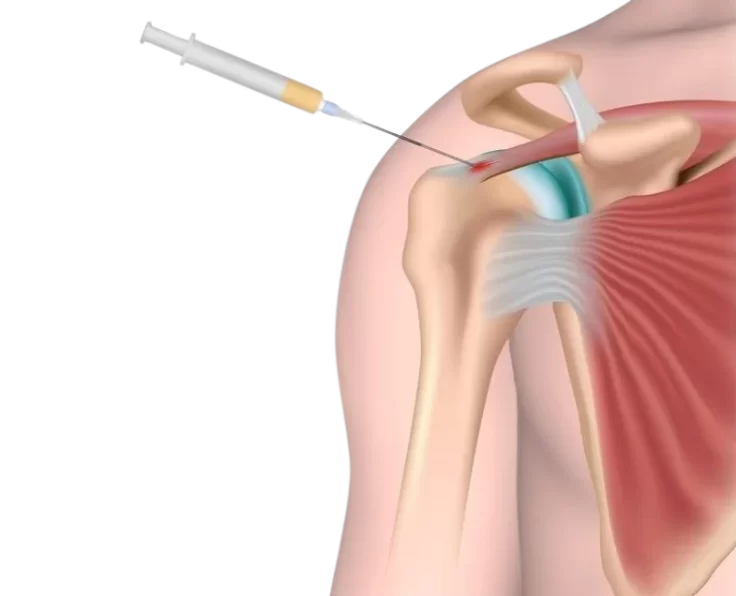

Hydrodilation of Shoulder

Hydro dilation is a treatment for joints that have become painful and stiff as a result of scar tissue build-up. It's most commonly used to…

PRP for Shoulder

Platelet Rich Plasma therapy, or PRP, is a non-healing muscle and tendon injury treatment option for people with SCI who have shoulder pain (Spinal Cord…